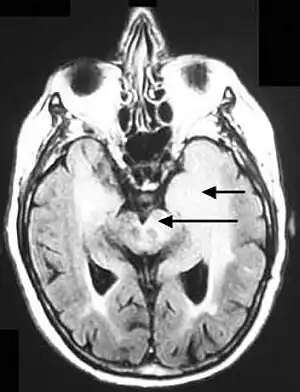

| Axial fluid-attenuated inversion recovery MRI image demonstrating tumor-related infiltration involving both temporal lobes (Short arrow), and the substantia nigra (Long arrow). | |

Before the advent of MRI, diagnosis was generally not established until autopsy. Even with MRI, however, diagnosis is difficult.[8] Typically, gliomatosis cerebri appears as a diffuse, poorly circumscribed, infiltrating non-enhancing lesion that is hyperintense on T2-weighted images and expands the cerebral white matter. It is difficult to distinguish from highly infiltrative anaplastic astrocytoma or GBM.